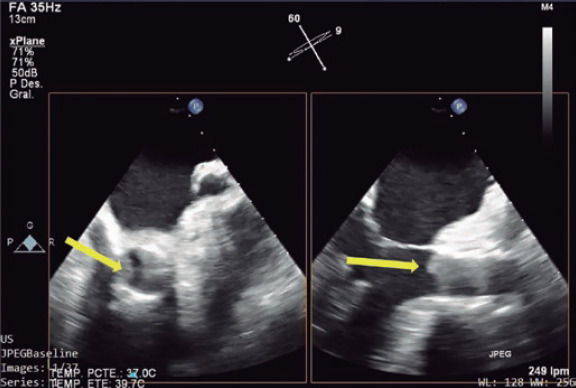

Abstract Image